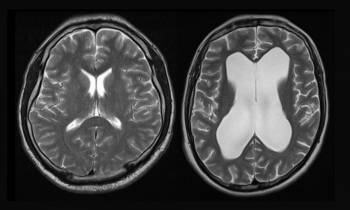

TECH | X-Pressure veut diagnostiquer l’hydrocéphalie

La jeune medtech toulousaine s’apprête à industrialiser son outil de diagnostic de l’hydrocéphalie avec le soutien financier de...

TECH | Braintale pense aux institutionnels

Première levée de fonds auprès d’investisseurs institutionnels pour la medtech strasbourgeoise qui mesure les altérations de la microstructure de la substance blanche du cerveau auprès de...